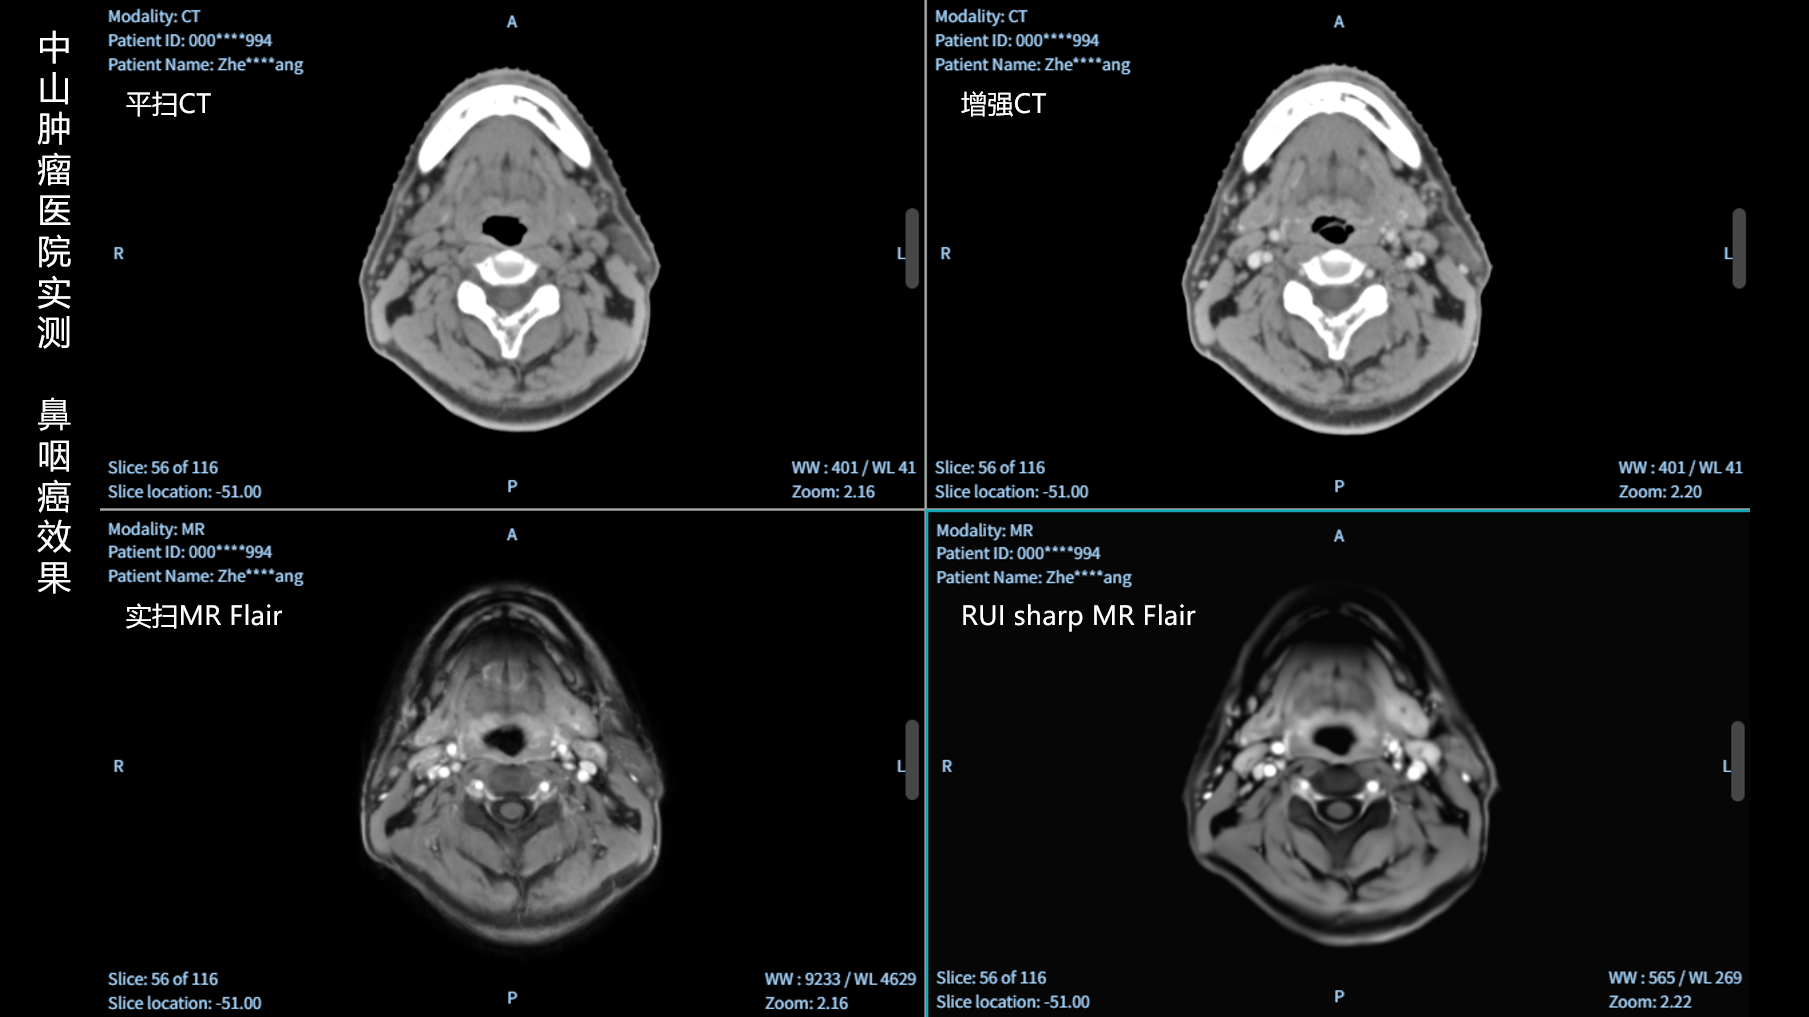

RUI sharp H(锐影)可在不依赖MRI的前提下,显著提升头部CT图像的软组织分辨率,为临床提供更高质量的辅助信息,尤其适用于MRI资源受限或较难配准的头颈部放疗感兴趣区勾画场景。

可大幅提高头部CT影像软组织分辨率,使肿瘤和周边器官显示更清晰,为放疗靶区勾画提供参考。

无需图像配准,CT和锐影图像同源,可匹配、叠加、"淡入淡出"显示。

实测效果